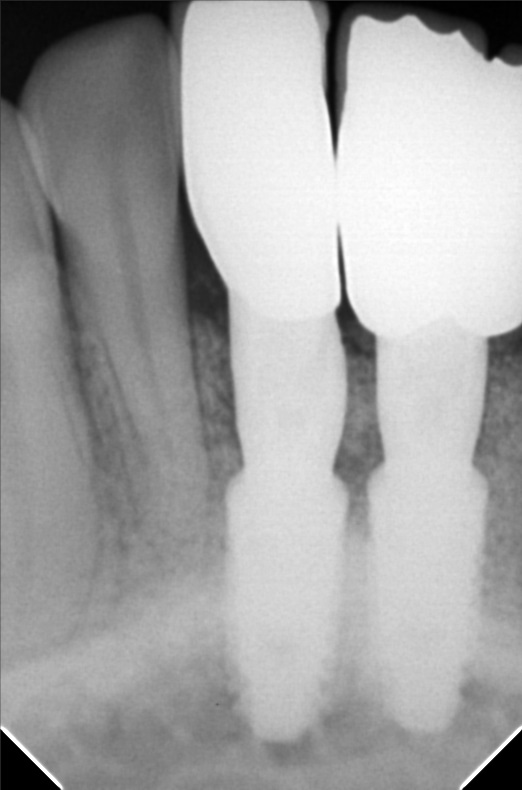

Edit Record Check our patient data records. Add patient information Patient Info Profile picture Last Name First Name Middle Name Birthdate Age Street Barangay City Country Zip Code Contact number Email Procedure 01/30/21 ICF - check up Feb 8,2021 - Implant 11/03/22- OP/OZONE/PAD feb,20,2021- removal of suture march 31,2021- LC 11 & 21 07/31/21 repair 41 zirconia resto 36CAOH/46 CAOH/43/34 OP June 4,2022 - OP / Xray 05/13/23- OP(Moderate); xray; ozone Oct 1 2023 op with air polisher noticed gum recession Removal of fiber splint on 42/43 05/07/24 Air polisher Xray OP 06/15/24 connective tissue graft harvested side: upper right quadrant w/ suture- monofilament absorbable 4/0 donor site: implant #41/32 buccal and lingual combination of monofilament absorbable 4/0 and nylon 6/0 non absorbable 06/22/24 check up 06/29/24 suture removal File raposa_donna_kelly_3.jpg File 2 raposa_donna_kelly_2.jpg File 3 raposa_donna_kelly_1.jpg File 4 donna_kelly.jpg File 5 june_42022.jpg File 6 raposa_donna.jpg File 7 raposa_donna_02.jpg File 8 img_2831.jpg File 9 File 10 File 11 File 12 File 13 File 14 File 15 File 16 File 17 File 18 File 19 File 20 Retain Record Retain Record Yes No Save Your Changes